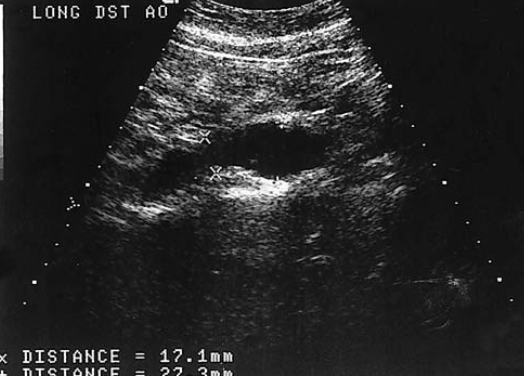

the pyloric canal is located is considered abnormal when the length exceeds

17 mm